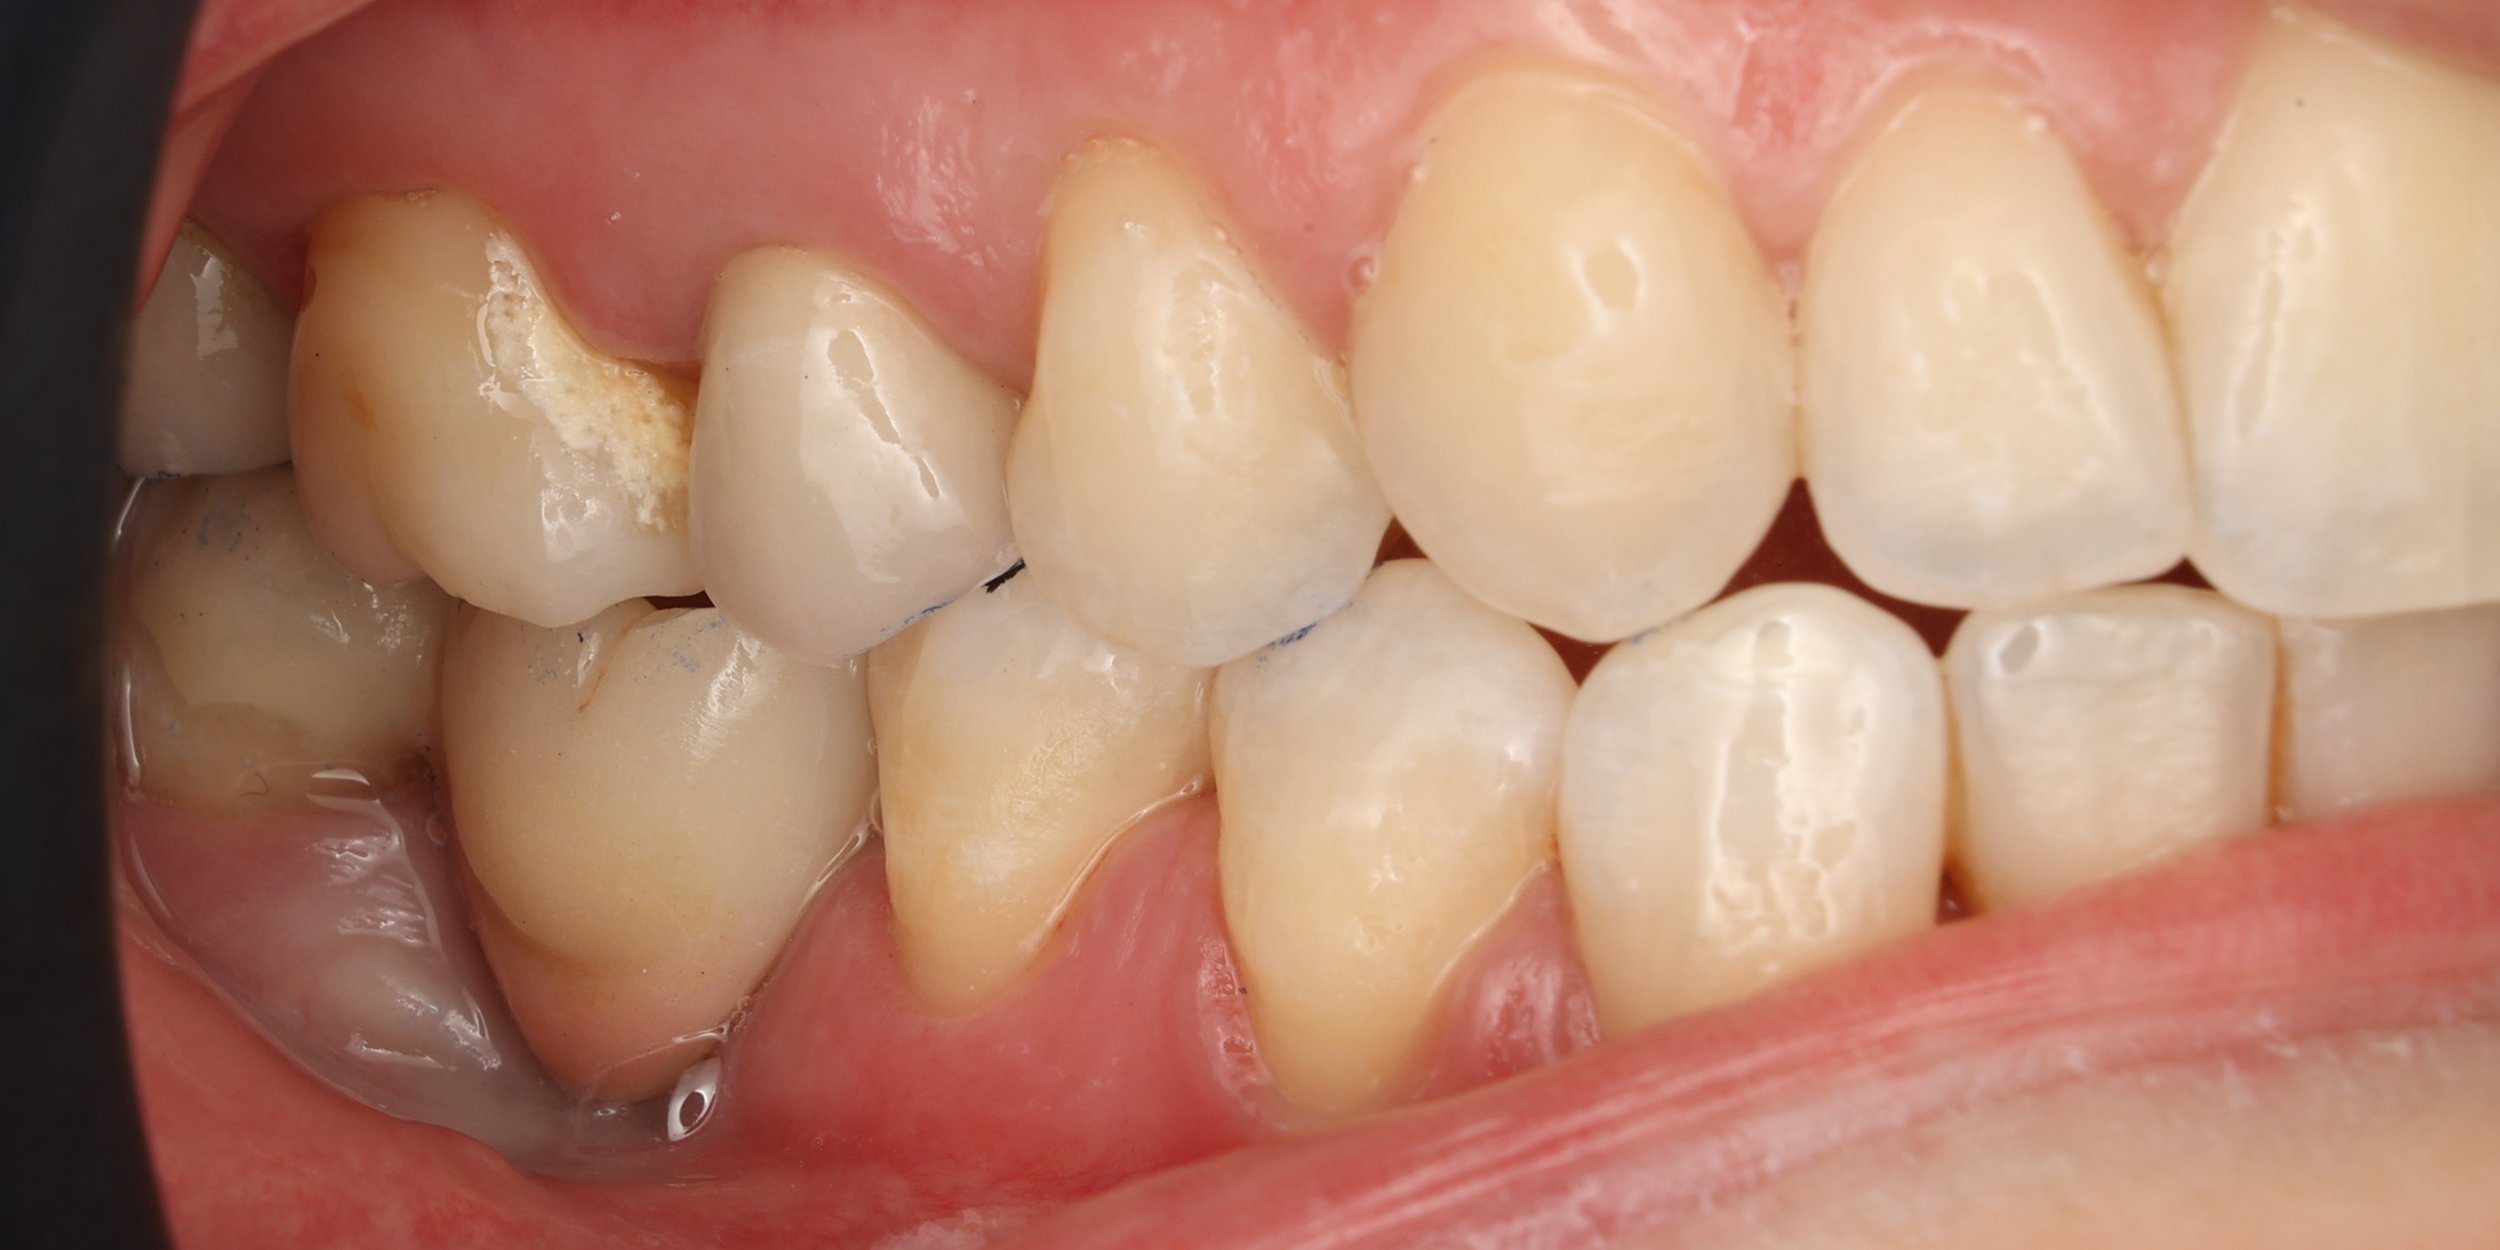

Relativement récents, les bridges collés cantilever postérieurs constituent une alternative fixe, fiable et véritablement minimalement invasive aux implants dans les secteurs postérieurs. Cette thérapeutique qui repose sur des indications bien précises est parfois débattue avec passion sur les réseaux sociaux ou dans les congrès scientifiques. Cependant des études cliniques existent, tout comme des recommandations validées dans des journaux internationaux. Leur succès repose sur des préparations et des principes biomécaniques rigoureux, pourtant simples à intégrer au quotidien. Cette intervention propose un guide clair et opérationnel incluant indications, étapes clés, protocoles d’adhésion et réglages occlusaux pour les mettre en œuvre avec confiance et reproductibilité.